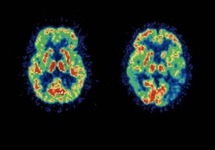

75-year-olds in the US, in other words, scored far better than their sun-starved age peers, and equalled the performance of Brits 10 years younger, according to the study, published in London-based journal BMC Geriatrics.

The tests measured instant and delayed recall of a series of ten common nouns such as "tree", "village," "baby," etc. Participants were also asked what day, date, month and year it was.

On a 24-point scale, US subjects scored 12.8 on average, compared to 11.4 for the English.

"The better cognitive performance of US adults was actually quite surprising," said Kenneth Langa, a researcher at the University of Michigan and the study's lead author.

"US adults have a higher prevalence of cardiovascular risk factors, which are generally associated with cognitive decline and poorer mental function."

Such risk factors include smoking tobacco, obesity, physical inactivity and high blood pressure.

Langa speculated that higher education and income levels in the United States may have compensated, resulting in sharper minds going into old age.

He also noted that American adults report significantly lower levels of depression than their British counterparts, a factor than can also affect cognitive skills.